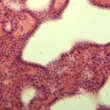

النسيج الظهاري الحرشفي البسيط (Simple squamous epithelium) يتكون من خلايا مسطحة ورقيقة تشبه الحراشف. هذه الخلايا توجد على الغشاء القاعدي وتتميز بقدرتها على تسهيل عمليات الانتشار والترشيح. يتواجد هذا النوع من الأنسجة في أماكن مختلفة من الجسم، بما في ذلك الأوعية الدموية (الشرايين والأوردة)، وبطانة القلب، والأوعية الليمفاوية، والحويصلات الهوائية في الرئة، والغشاء الطبلي في الأذن، ومحفظة بومان في الكلى.

يتميز النسيج الظهاري الحرشفي البسيط بجدران خلوية رقيقة تسمح بتبادل الجزيئات بكفاءة عبر الغشاء الخلوي. شكله المسطح يوفر سطحًا أملسًا يقلل الاحتكاك، مما يسمح للسوائل بالتحرك بسرعة وسهولة فوقه. على الرغم من أن جميع الخلايا في النسيج متشابهة، إلا أنها قد تختلف قليلاً في تفاصيلها الدقيقة.